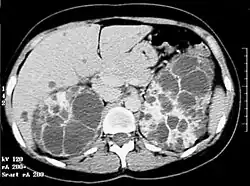

La polykystose rénale autosomique dominante (PKD), aussi appelée maladie rénale polykystique ou encore Rein polykystique autosomique dominant est la plus fréquente des maladies héréditaires monogéniques du rein. Elle se caractérise par l’apparition lente et progressive de kystes principalement au niveau des reins.

Les dilatations kystiques atteignent à la fois les canalicules biliaires et les néphrons. Les complications rénales de cette polykystose sont liées au développement, à la désorganisation, et à la destruction du parenchyme rénal normal par les kystes rénaux. La sévérité de l'atteinte rénale est directement corrélée au volume des reins. L’aspect « in utero » est rare et ressemble souvent à une polykystose rénale type récessif mais d’apparition est beaucoup plus tardive (vers 28, 32 semaines) avec absence d’anomalie du liquide amniotique. Une échographie rénale des parents est une aide pour le diagnostic. Tous les individus porteurs d'une mutation dans le gène PKD1 ou PKD2 développeront des kystes rénaux (pour les formes liées à PKD1, l'absence de kystes rénaux après 30 ans élimine le diagnostic.

Les kystes hépatiques sont fréquents et leur prévalence varie avec la méthode diagnostique utilisée (beaucoup plus fréquent à l'IRM, plus sensible, qu'à l'échographie. Ils sont le plus souvent silencieux.

Le scanner n'est pas nécessaire en première intention, même s'il visualise parfaitement les kystes, qu'ils soient rénaux ou hépatiques. l'IRM permet de quantifier le volume rénal, ce dernier étant corrélé avec le risque évolutif[16].

L'augmentation de la taille des deux reins est, en règle générale, symétrique[17].